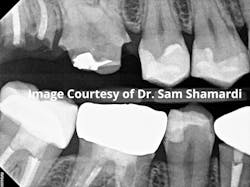

Patient procedure completed: Extraction of residual root tips from fracture of tooth no. 2 and crown lengthening for no. 3.

Crown lengthening is advised in this specific case because the decay was so large that the natural tooth structure left behind is not the recommended amount to properly hold the crown. At least 3 to 4 mm of sound root structure must be exposed below the most apical extent of the proposed restoration. Crown lengthening can also be used to remove excess gingiva for "gummy" smiles or provide better esthetics, especially around anterior veneers or crowns.